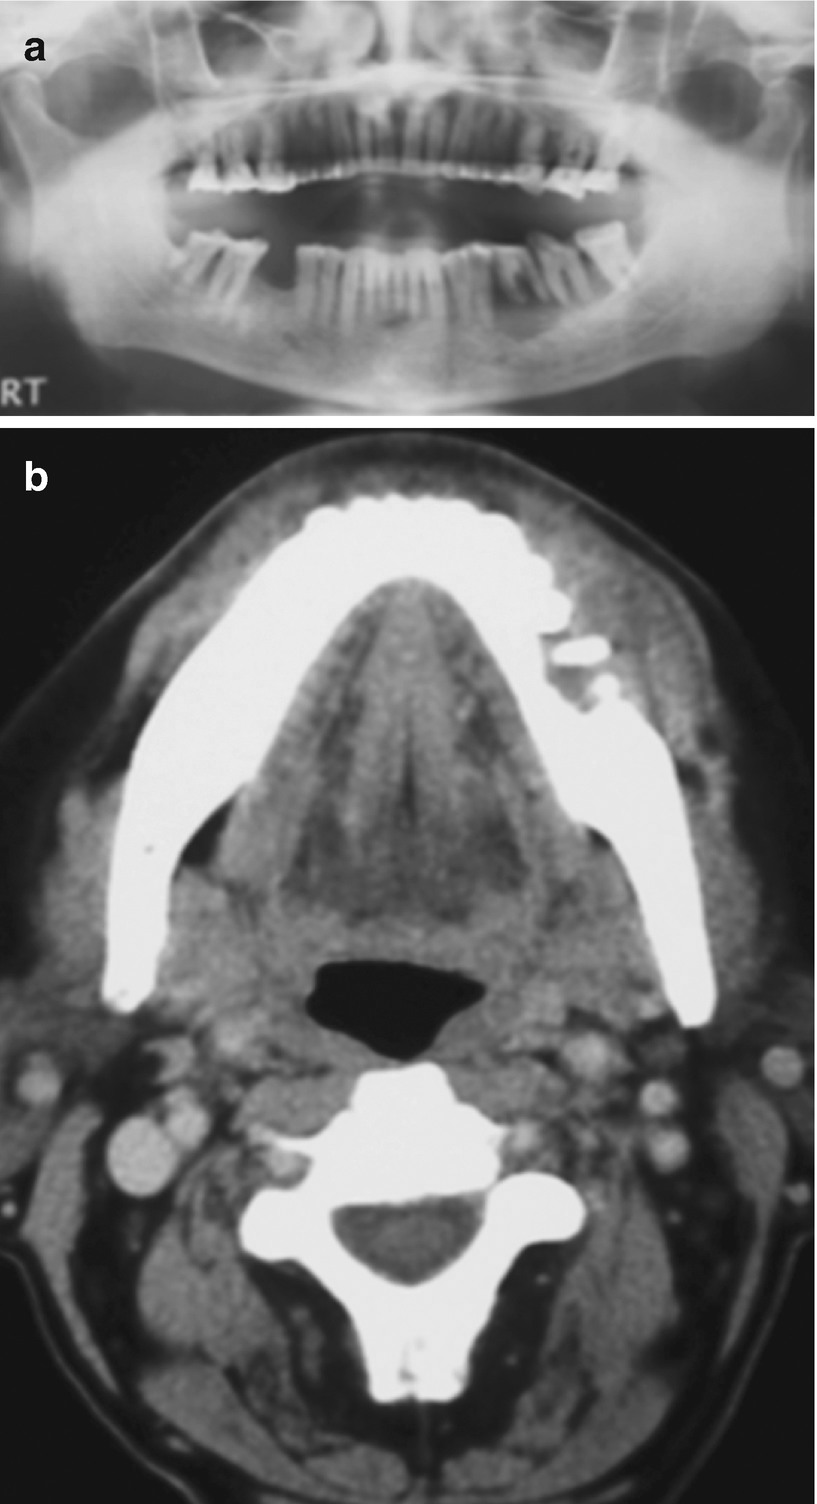

Squamous Cell Carcinoma Of The Oral Cavity Radiology Case Radiopaedia Org

Squamous Cell Carcinoma Of The Oral Cavity Radiology Case Radiopaedia Org from prod-images-static.radiopaedia.org